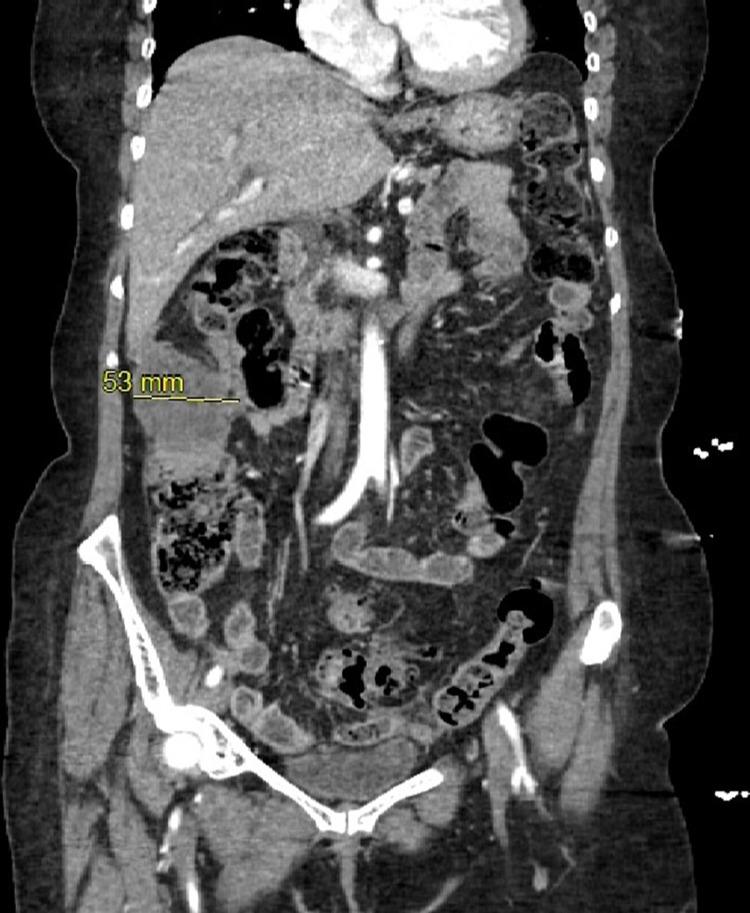

Mesotheliomas are a rare malignancy of the serosal membrane. Mainly it affects the pleural surfaces followed by the second most common location, "peritoneum." The disease follows an aggressive pattern of spread, and by the time the diagnosis is established, the condition significantly spreads to distant locations. Diagnosis of malignant peritoneal mesothelioma is typically made by tissue biopsy. The standard treatment is radical resection; however, patients have benefited from several other modalities. The current case report describes a unique case of malignant mesothelioma, biphasic peritoneal mesothelioma (BPM), which comprises less than 25% of all peritoneal mesotheliomas. The diagnosis and treatment do not differ from other subtypes; however, the prognosis is poor, and if untreated, the survival is typically less than six months.

间皮瘤是一种罕见的浆膜恶性肿瘤。主要累及胸膜表面,其次是第二常见的部位“腹膜”。该疾病呈侵袭性扩散模式,在确诊时,病情已显著扩散至远处。恶性腹膜间皮瘤的诊断通常通过组织活检进行。标准治疗方法是根治性切除;然而,患者也从其他几种治疗方式中获益。本病例报告描述了一例独特的恶性间皮瘤,即双相性腹膜间皮瘤(BPM),其在所有腹膜间皮瘤中占比不到25%。其诊断和治疗与其他亚型并无差异;然而,预后较差,如果不进行治疗,生存期通常不到六个月。